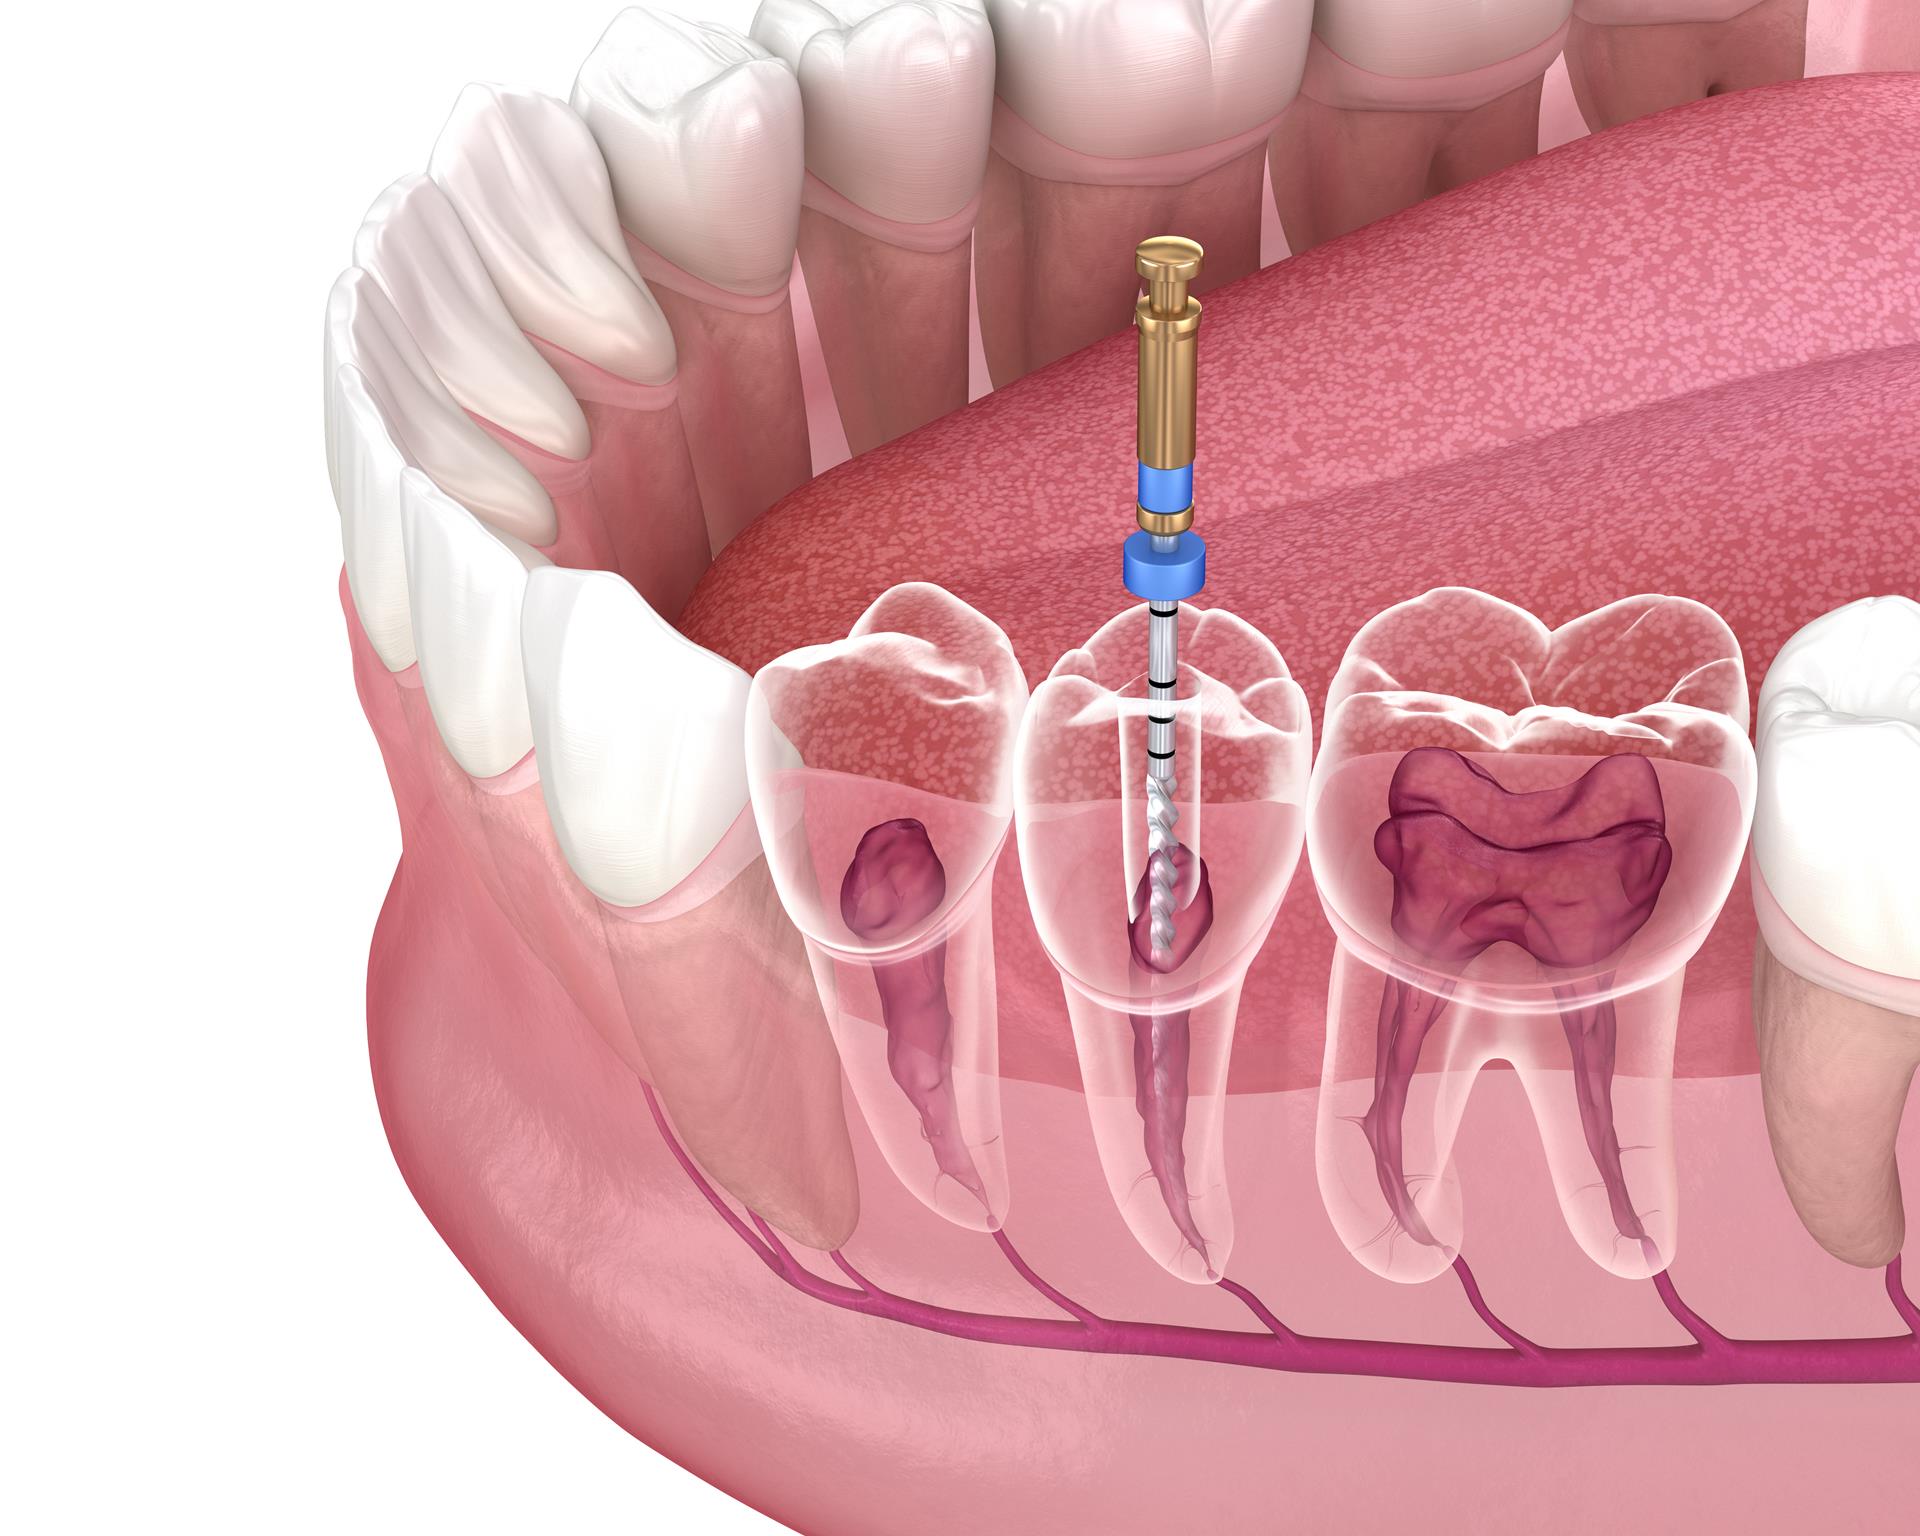

We are proud to offer our patients the latest in root canal therapy. A root canal is a procedure that extracts decayed pulp from the central part of the tooth, reshapes the canal and replaces it with strengthened filler.

The root canal procedure involves the following steps:

- The tooth is opened to allow for removal of infected or dead dental pulp.

- The tooth is comprehensively cleaned, including any cracks and canals.

- With special tools, the doctor reshapes the canals.

- The tooth is filled again with cutting edge biocompatible filling material.